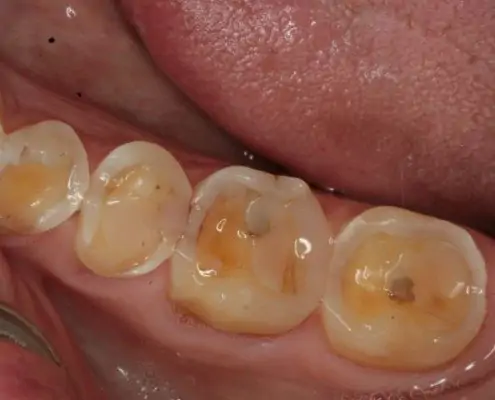

AvantAprès

Identifier les signes d’érosion dentaire

Les érosions dentaires peuvent être détectées lors d’un examen dentaire ou d’un détartrage. Des dents jaunies, une sensibilité accrue aux températures chaudes ou froides, ou des douleurs dentaires peuvent être des signes d’érosion dentaire.

Nous utilisons particulièrement les dernières techniques de dentisterie micro invasive permettant de restaurer de telles lésions en préservant un maximum de matière dentaire résiduelle.